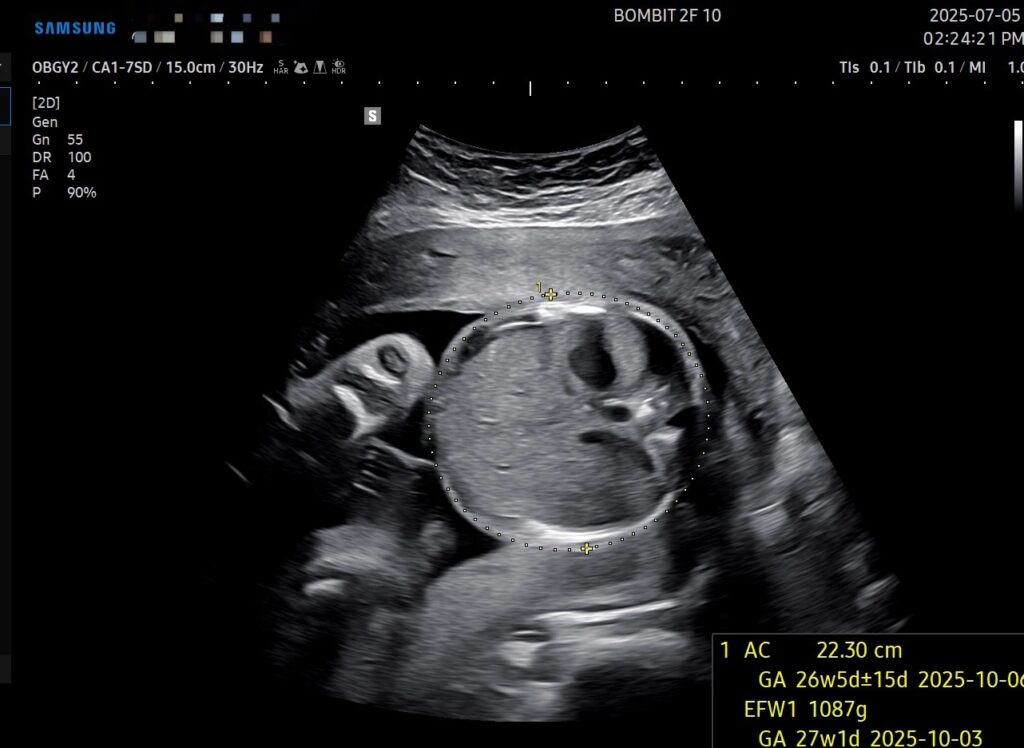

지금 단비는 어언 26주.

단비는 많이 우량해졌다.

주수에 비해 10일~2주 정도 더 크다고 한다. 초음파 본 날 기준, 900g 정도가 표준 무게라는데 단비는 1kg 가 훌쩍 넘어버림..

단비 크기도 큰 데다가 역아라고 해서 조금 걱정이 된다. 그래도 아직은 주수로 26주이고 34주 전까지만 잘 돌면 된다니 일단 그 때까지 지켜봐야 할 것 같다.

이건 초음파 사진!